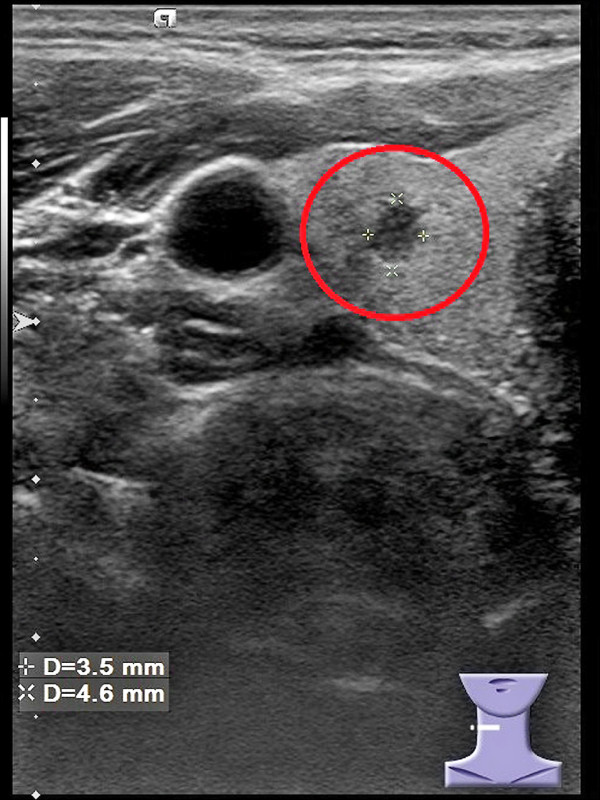

39歲陳先生參加公司健檢時,特別安排甲狀腺超音波檢查,意外發現右側甲狀腺有1個小結節(圖1),隨後轉診至新陳代謝科,接受細針穿刺檢查,確診為「甲狀腺微小乳突癌」(圖2),經手術切除右側甲狀腺及峽部,術後恢復情況良好。

陳先生就醫時,自述身體狀況良好,過去從未接受過甲狀腺檢查,這次因公司安排健檢,經醫師建議加做頸部超音波,結果影像顯示他的右側甲狀腺有1個小結節,長寬高約4.1x3.5x4.6毫米,因此轉診至新陳代謝科門診進一步諮詢。

經再次檢視影像,發現結節有多個異常特徵,包括結節高度大於寬度、結節是實心、結節是低回音等,雖然結節內沒有鈣化點、邊緣也規則,但還是高度懷疑是「甲狀腺微小乳突癌」,隨後在超音波導引下,進行細針穿刺檢查,1星期後報告出爐後,果然證實是甲狀腺乳突癌。